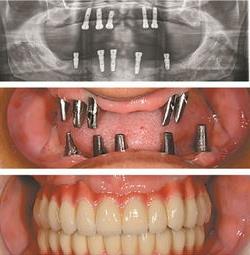

3.種植義齒修復。種植義齒就是在牙槽骨里面種一個人工牙根,然后在上面做一顆假牙。

種植義齒有很多優點:不損傷兩邊的鄰牙,不增加鄰牙的負擔,咀嚼效率高,可減緩牙槽嵴的萎縮,不會出現齲齒,不會有牙髓炎,牙周炎的患病率也低。種植義齒可以稱為人類的第三副牙齒。

種植義齒的缺點:費用較高,因為對材料的要求非常高,而且周期比較長。

種植牙是牙齒缺失修復的首選

種植牙的成功率很高,且維護得當使用終身都是沒問題的,當然不是每個人都能用這么長時間。有部分病人會有這樣的顧慮,我別的牙掉了,如果只剩這個種植牙,是不是會影響我鑲滿口假牙呢?其實,種植牙對鑲牙是不會有任何影響的。如果其他牙掉了,可選擇再種一顆。如果由于身體原因或經濟原因,不愿意再種了怎么辦?沒關系,這些種植牙一樣可以利用,就像前面給大家講的,如果別的牙缺失了,種植牙還在,也可以利用這幾顆種植牙來固定別的假牙,所以只要有牙在,都可以利用,有種植牙,一定比沒有種植牙效果要好,所以種植牙“太結實”無需憂慮,它不僅不會影響你鑲滿口假牙,而且會有利于鑲牙。